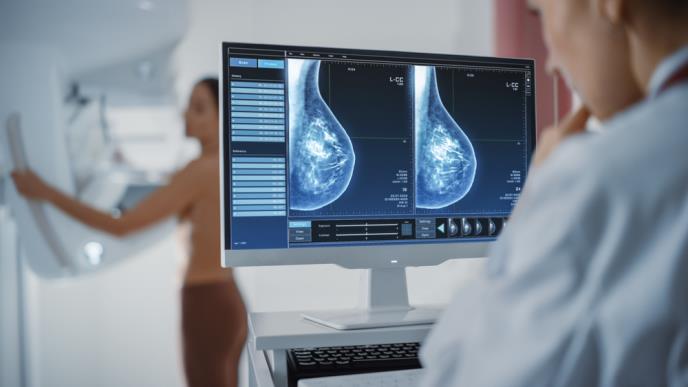

Drugim rečima, gustina dojki se odnosi na sastav tkiva dojke. Veća gustina se ne može osetiti dodirom, već se otkriva mamografijom. Guste dojke imaju više žlezdanog i vezivnog tkiva, a manje masnog, što može da oteža uočavanje promena poput čvorića ili tumora na mamografskom snimku.

- Kod gustih dojki i normalno tkivo i eventualni tumor izgledaju belo na mamografskom snimku, pa lekari često ne mogu da uoče male promene, jer se one 'gube' u gustini. Zato je kod ovih pacijentkinja potrebna dodatna preciznost, posebno tokom preventivnih pregleda na rak dojke - objašnjava dr Viduši.

Pošto i tumor i gusto tkivo izgledaju slično na mamografiji, promene mogu da ostanu neprimećene. Zbog toga je važno da žene sa gustim dojkama razgovaraju sa svojim lekarom o dodatnim opcijama za skrining, savetuje.